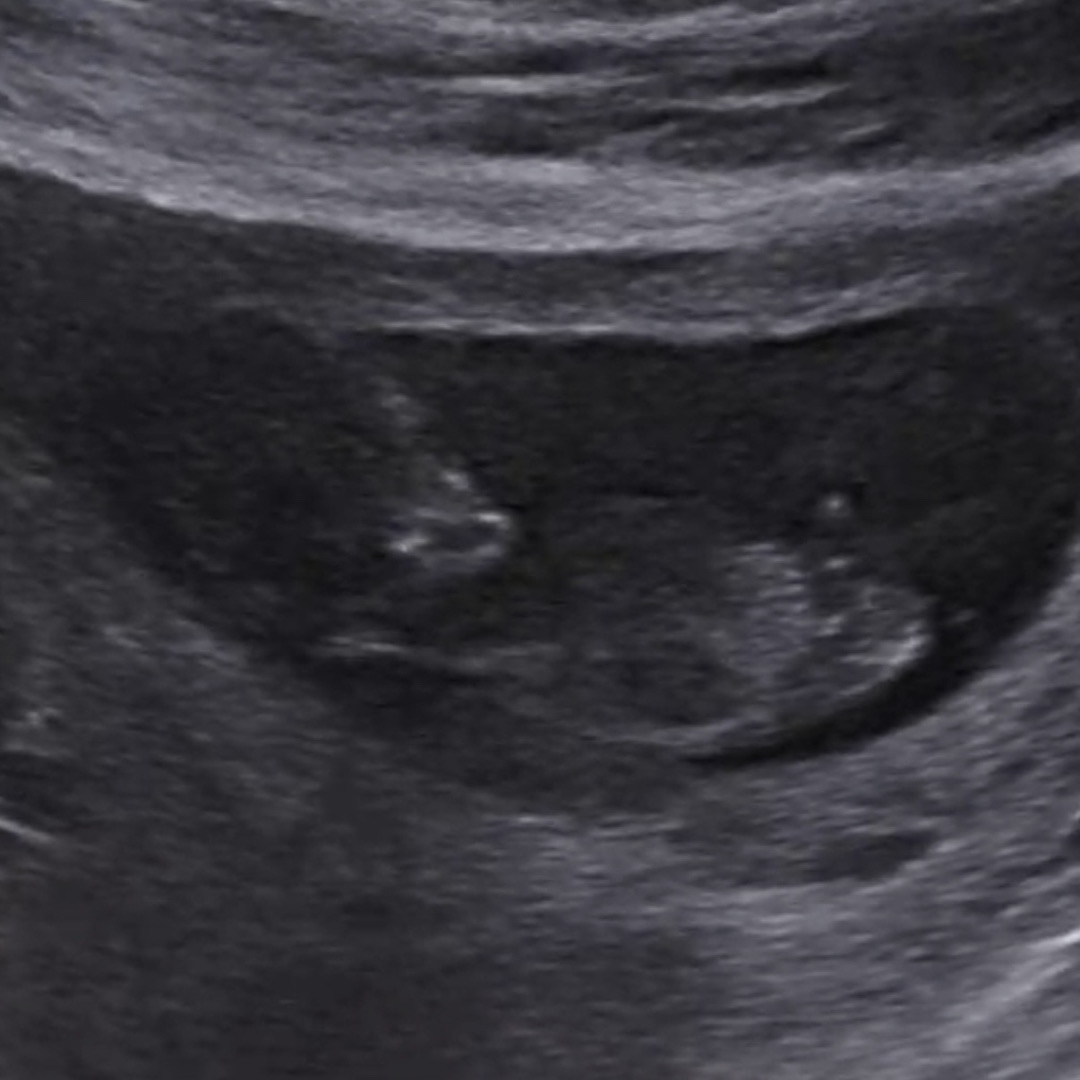

각도법 봐주실 수 있을까요?!

저는 아무리봐도 각도법 보는 방법을 모르겠어요😅 더 기다려봐야할까요??